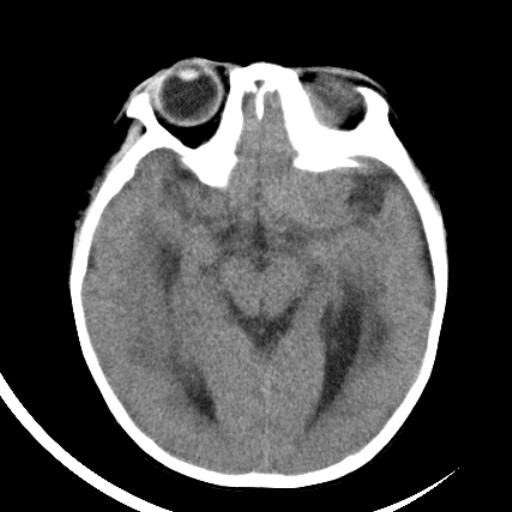

双侧脑室前后角周围白质片状低密度影,双侧侧脑室旁、双顶叶皮层及皮层下多个小原点状钙化灶,不除外torch感染。右顶叶脑回似乎较对侧大,建议mri检查以除外脑发育异常。

考虑:1、巨脑回畸形(皮质明显增厚+脑回明显增宽+白质减少)。

2、torch综合征(室管膜下钙化+白质内及皮髓质交界处多发钙化)。